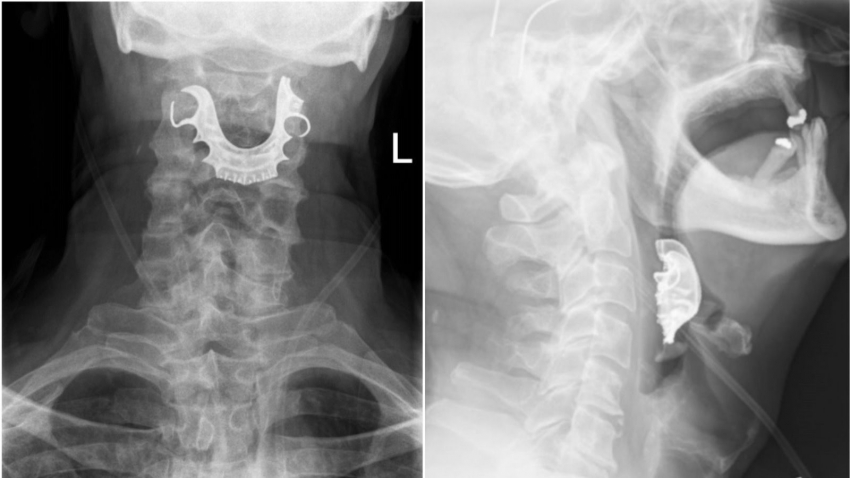

हे जेव्हा आजोबांना सांगण्यात आलं तेव्हा ते म्हणाले की माझी कवळी ऑपरेशनपासून हरवली आहे. हे समजताच त्यांच्या घशाचा एक्स-रे काढण्यात आला. यावेळच्या एक्स-रे मध्ये त्यांची हरवलेली कवळी त्याच्या घशात अडकल्याचं उघड झालं.

मंडळी, शस्त्रक्रियेच्या वेळी अनेस्थेशिया दिल्यानंतर त्यांची कवळी त्याच्या घशात पडली आणि त्यांने ती नकळत गिळली होती. आजोबांवर तातडीची शस्त्रक्रिया करण्यात आली. ६ दिवसानंतर त्यांना घरी सोडण्यात आलं.

या गोष्टीचा इथेच अंत होत नाही. काही आठवड्यांनी ते पुन्हा हॉस्पिटलमध्ये आले. यावेळी पण ते रक्त ओकत होते. डॉक्टरांनी तपासल्यावर समजलं की घशात ज्या ठिकाणी कवळी अडकली होती तिथली रक्तवाहिनी फाटली आहे. यानंतर त्याच्यावर दुसरी तातडीची शस्त्रक्रिया करण्यात आली. ६ दिवसानंतर त्याच्यात सुधारणा दिसू लागल्या. यावेळी आखरे त्याचा त्रास संपला होता.